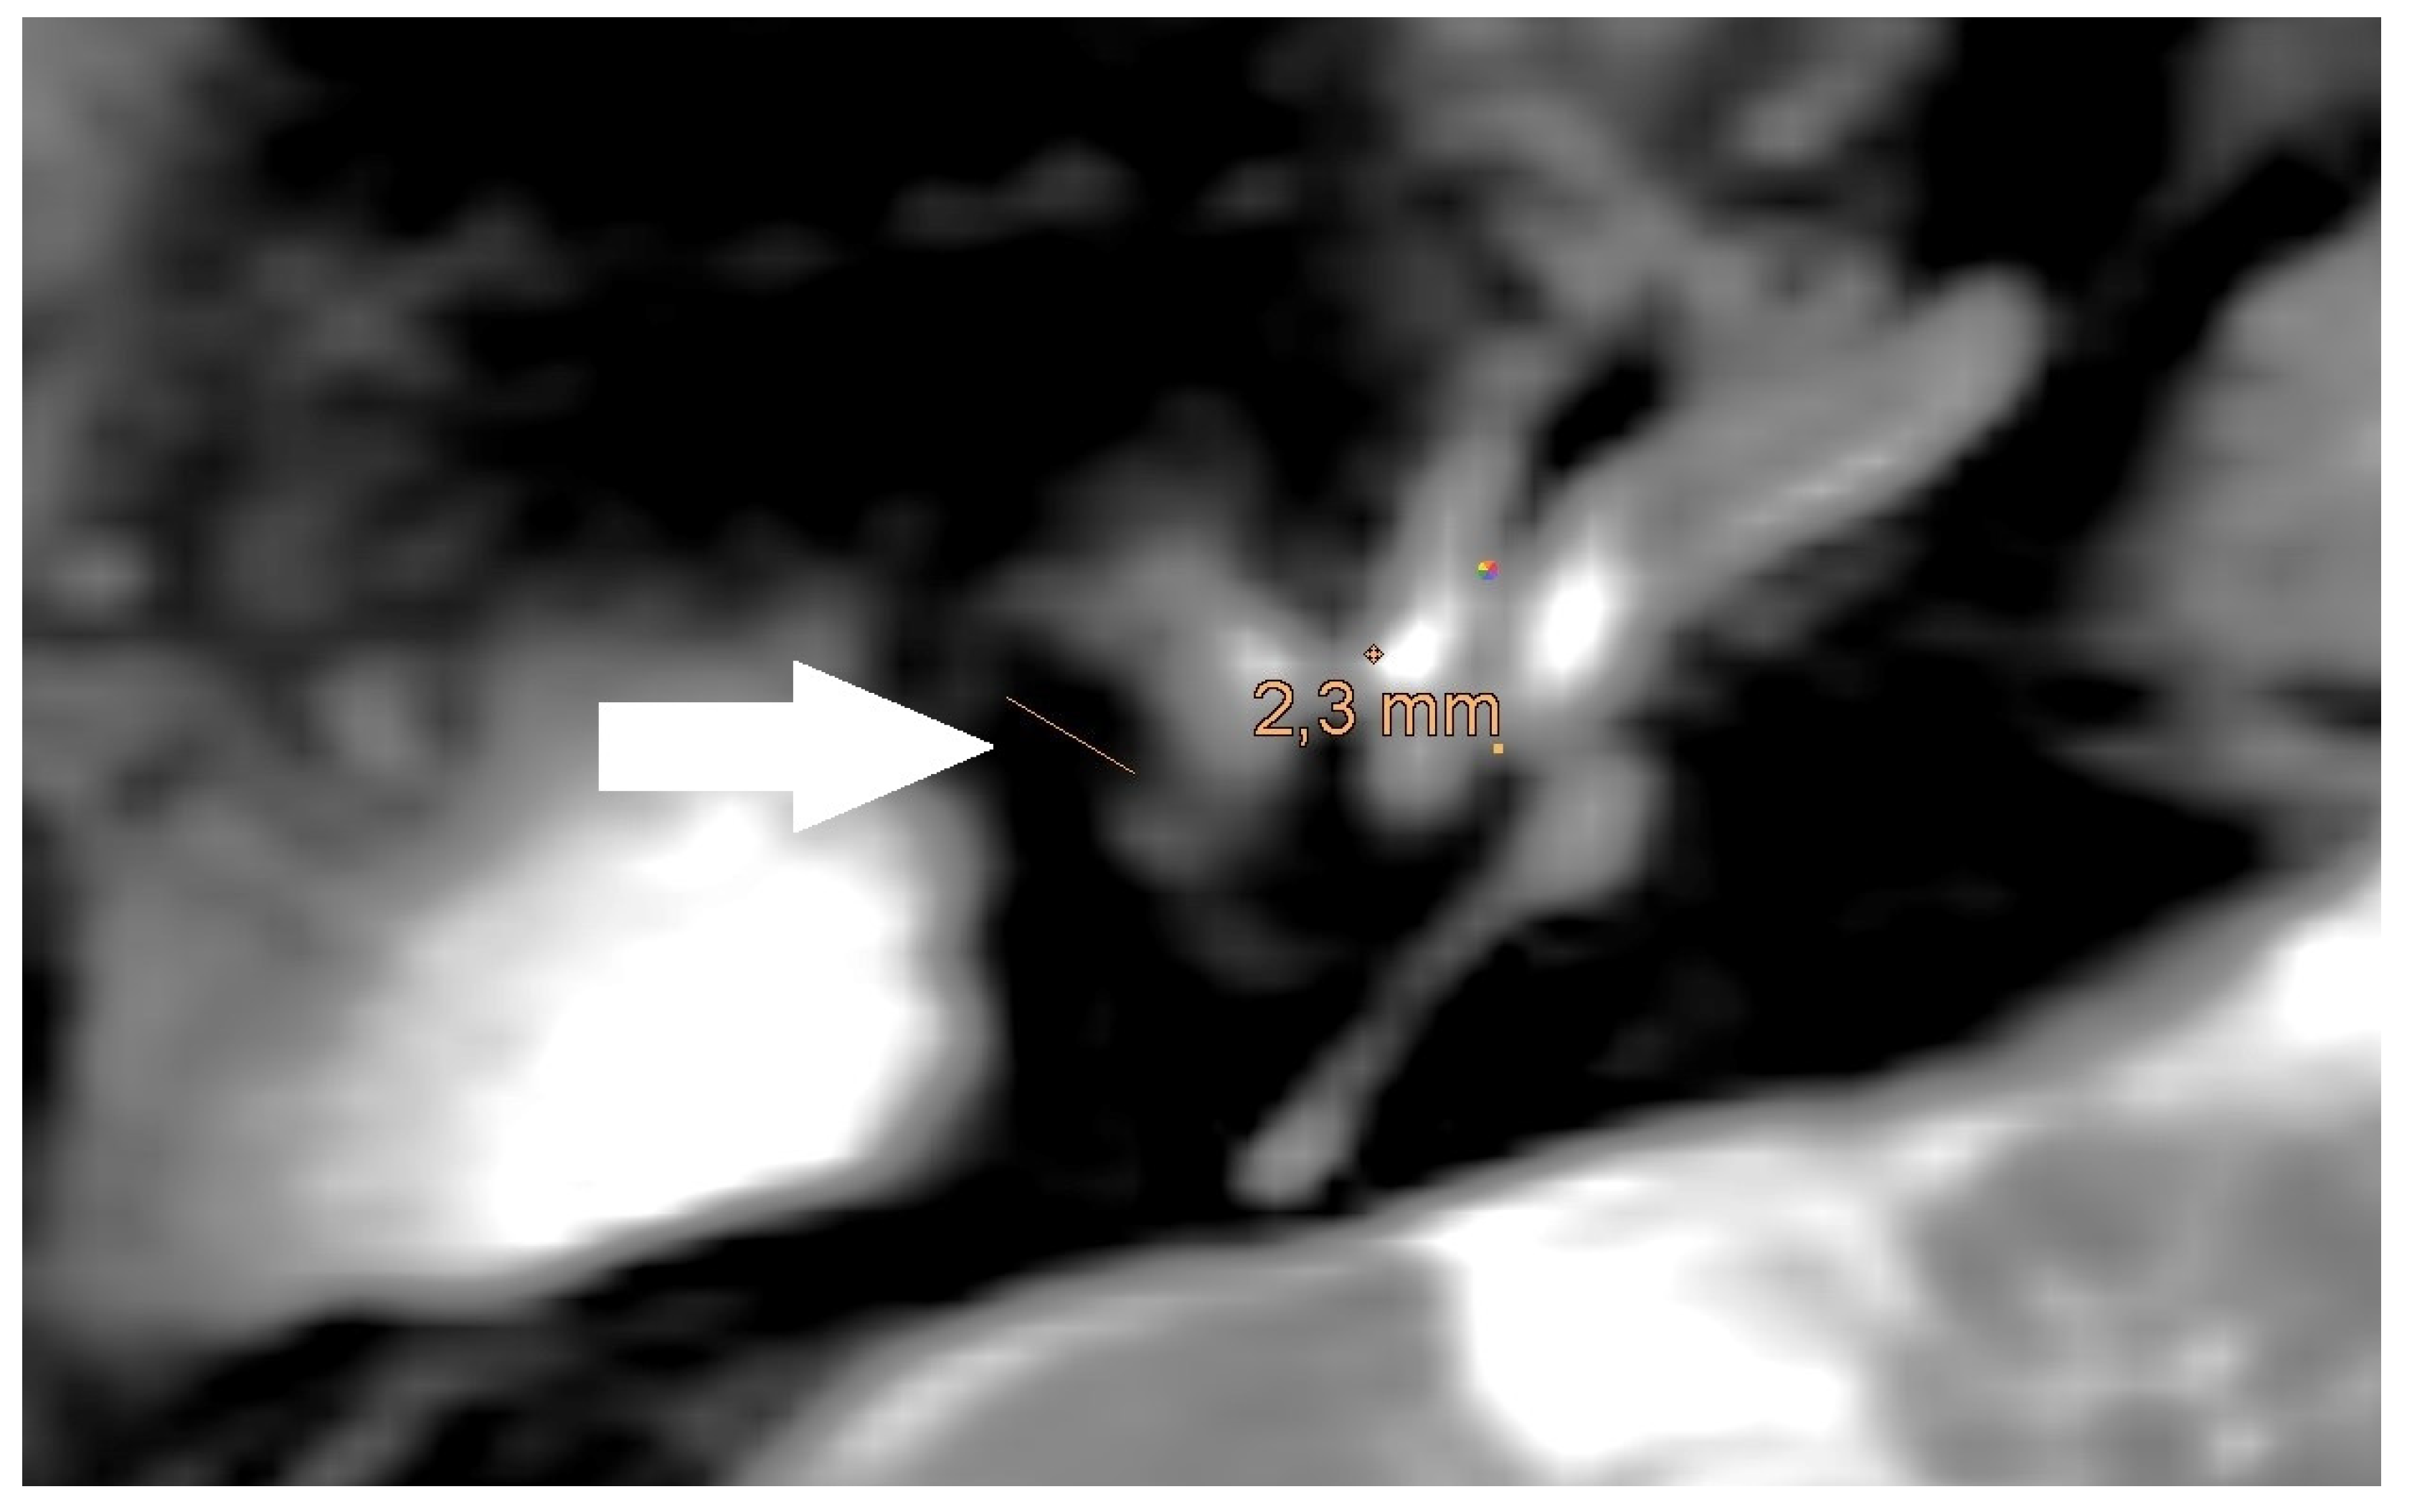

| Size of artifact | 3.60 (sd = 1.01, min = 2.50, max = 4.50) | 3.11 (sd = 0.54, min = 2.20, max = 4.50) | 4.74 (sd = 0.77, min = 3.90, max = 6.10) |

| PORP | 2.0 mm | 3.1 mm | 5.4 mm |

| TORP | 3.6 mm | 4.7 mm | 7.2 mm |

| Mesh | 0.1 mm | 3.6 mm | 5.8 mm |